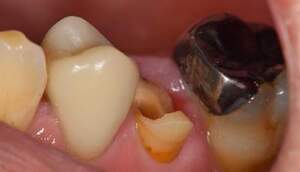

カリエスを取り除くと、遠心の歯質が歯肉縁下になりました。

MTM開始直後と、終了後です。フックの位置が変わっているのがわかると思いますが、それが歯が動いた証拠となります。

MTM中。頬側には審美面の回復のために仮歯がついています。

歯からはフック、隣り合った歯にはワイヤーが渡してあります。そこにゴムをひっかけて歯を挺出させます。